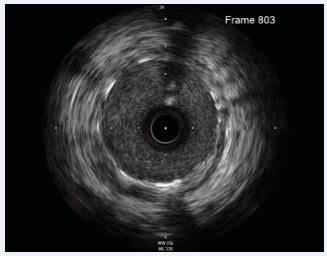

A 3.5 x 36 mm Biomatrix stent was deployed to cover the proximal LAD, overlapping with the previous mid-LAD stent. IVUS confirmed LAD diameter at 4.5 mm and a 4.75 mm diameter at the left main stem. (Distally with previous LAD stent and proximally to cover whole LMS.) (IVUS measurement). A 3.5 x 29 mm Biomatrix stent was deployed to overlap with the ostium of the left main stem. A 4.5 mm NC balloon was used at high pressure from just distal to the diagonal to the LAD ostium (Figure 4 and Figure 5).

Figure 5: Final IVUS post stent deployment shows well opposed and expanded stents with resolution of haematoma